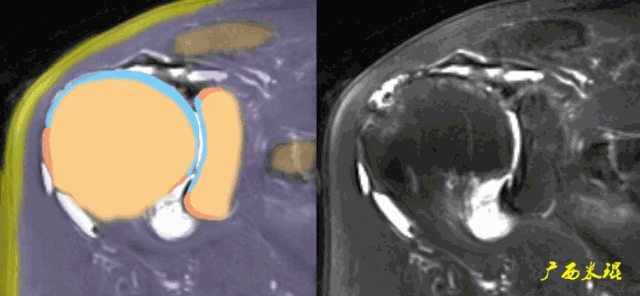

肩关节MRI检查扫描平面

(3)平行于关节盂/垂直于盂肱关节,主要评估盂唇,同时兼顾肩胛下肌、冈下肌及小圆肌。

正常肩袖的MRI表现

各个序列肩袖均表现为均匀的低信号,是肌腱的延续。